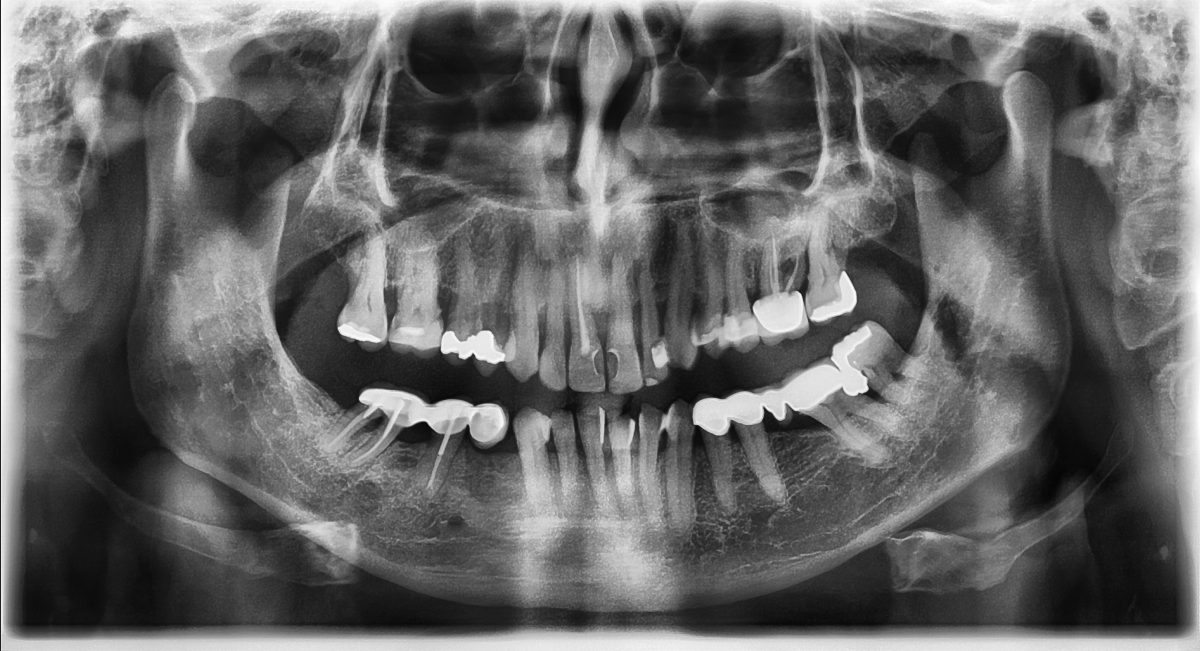

Firstly, we take an x-ray to accurately check the root canals of your tooth and make sure there are no signs of infection in the surrounding bone. We plan your treatment, letting you know of each stage.